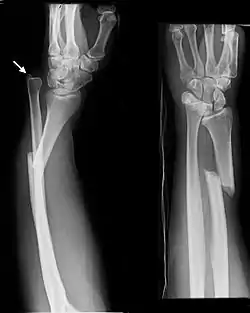

كسر غالياتزي[1] (بالإنجليزية: Galeazzi fracture) هو كسر في الثُلث القاصِ لعظمة الكعبرة مع وجود خلع في المفصل الكعبري الزندي القاصي.[2]

![]() كسر غالياتزي | |